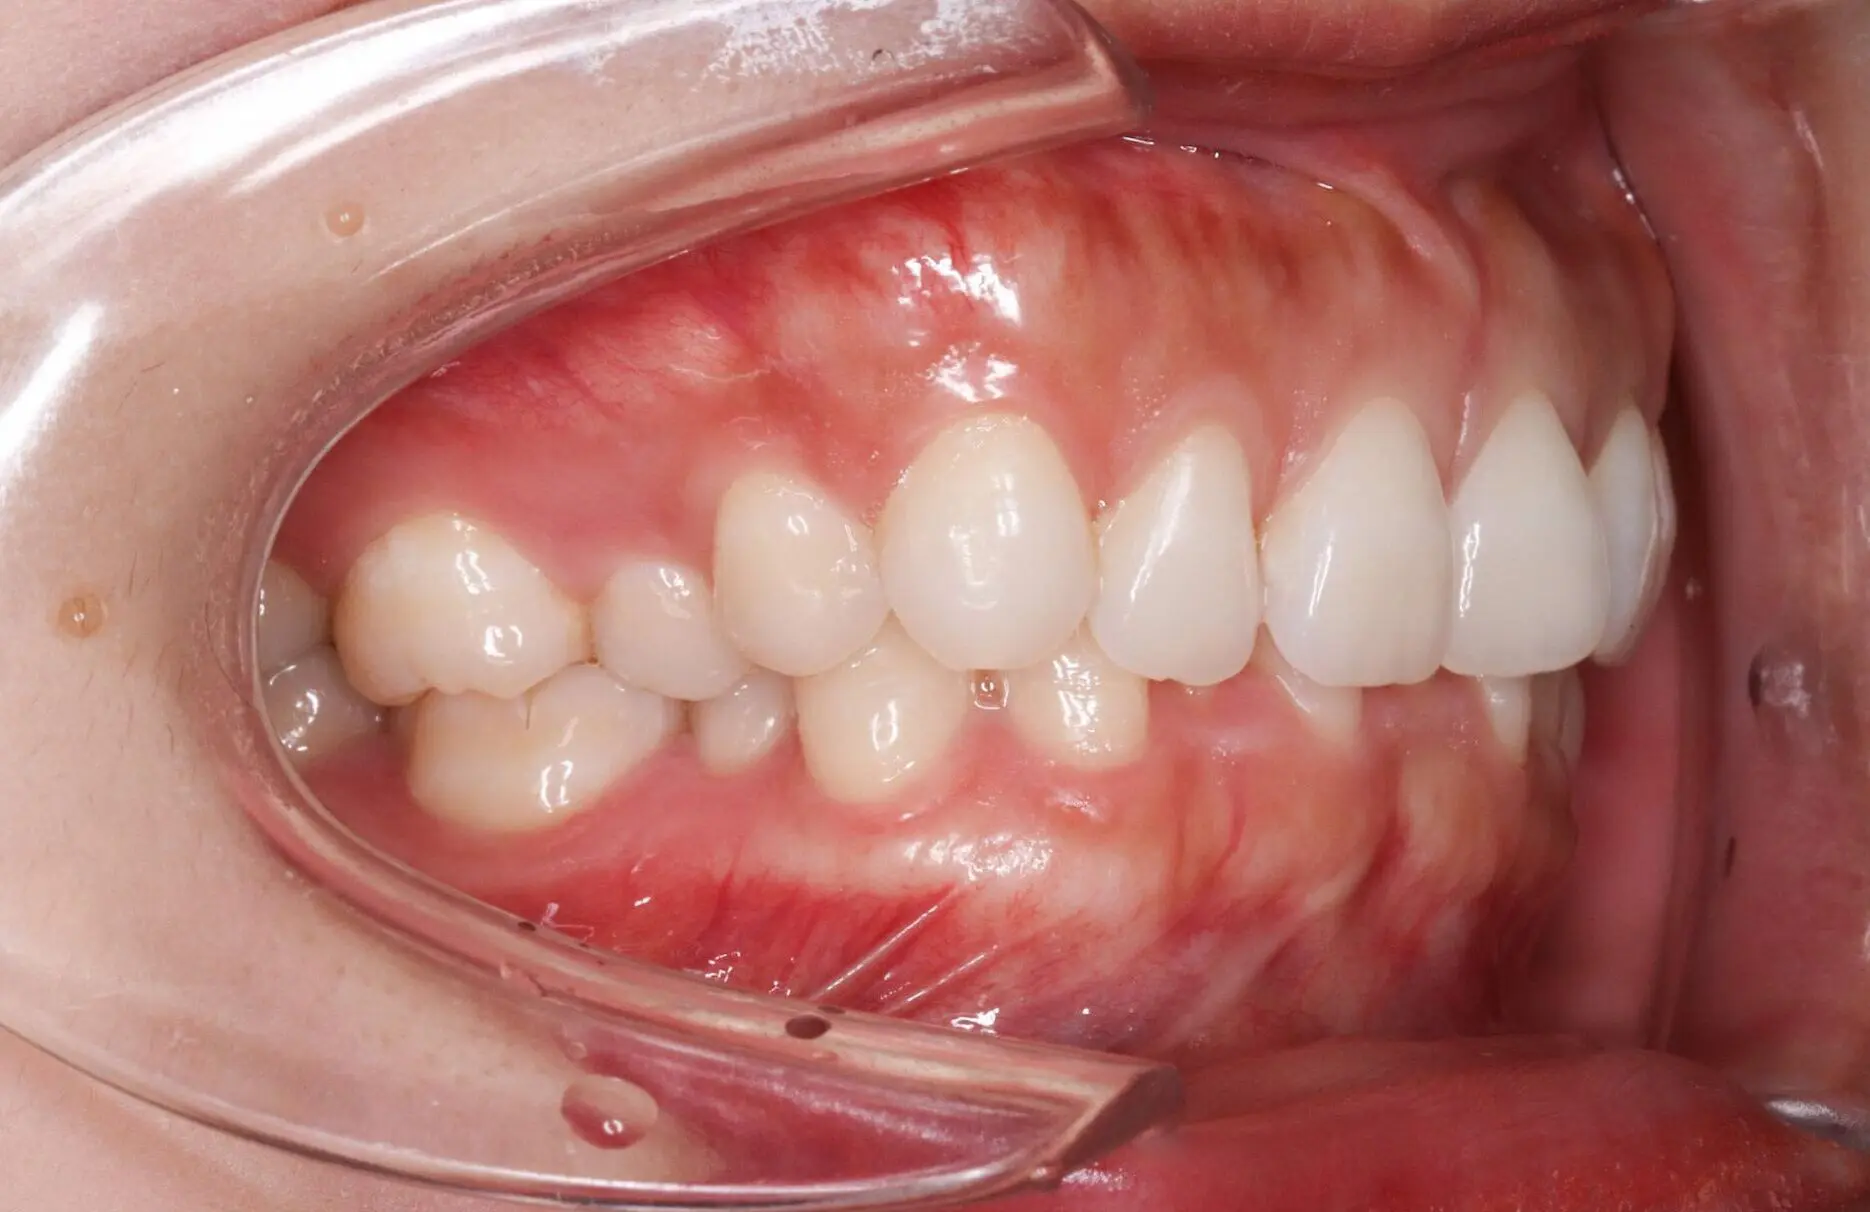

Before

After